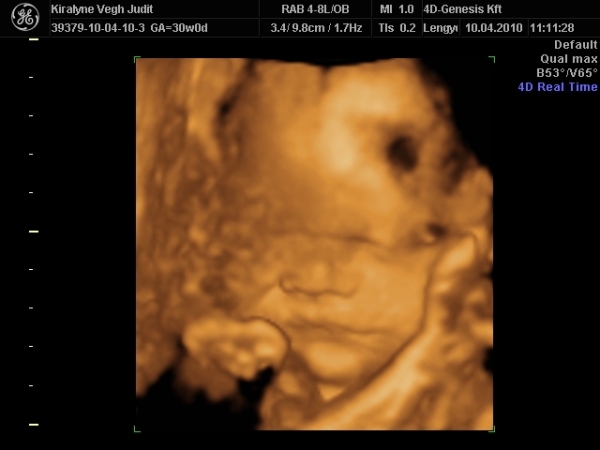

4D-re holnap megyünk 11-re, utána meg tervezünk egy kis csavargást. :lol: :lol: :lol:

Ma jól elfáradtam. Voltunk 4D-n, a várban és a Csodák palotájában. Rengeteget sétáltunk, nem érzem a lábamat.

A lényeg, hogy Izi baba nagyon jól van,

Babócám fejjel lefele, idézem: "méhlepény olyan távol van a méhszájtól, mint Makó Jeruzsálemtől." :oops: :oops: :oops:

Szóval nem értem a szerdai uh-ot. :oops: :oops:

"0" fokban érett a lepény, 1741g kis csöppségem, combcsont mérete alapján már 32 hetesnek felel meg. Amúgy minden mérete alapján 1 héttel idősebb. Magzatvíz átlagos. És tiszta apja. :lol: :lol: :lol: :lol:

És a képek.